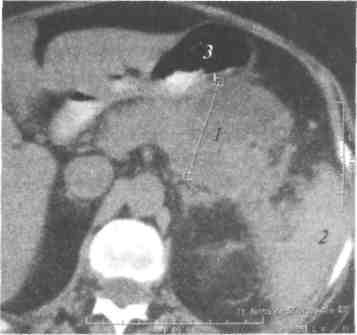

КТ диагностика тубоовариального абсцесса: Подходы и изображения

Раздел: Объективный взгляд